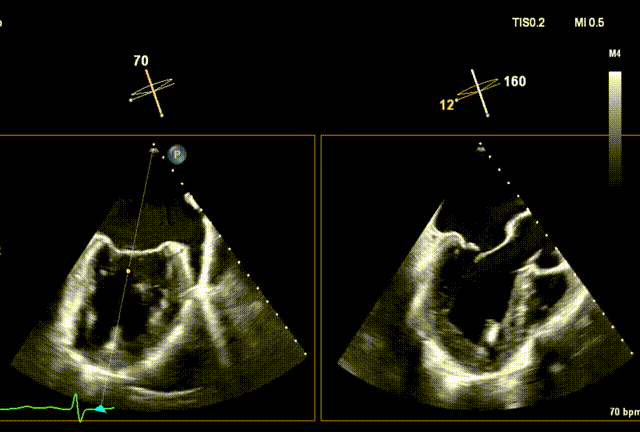

手术回顾

3D切面调整位置及钟向

3D再次确认位置及钟向

术后Xplane彩色图像

术后3D动图

夹合后二尖瓣反流量0+,平均跨瓣压差3mmHg